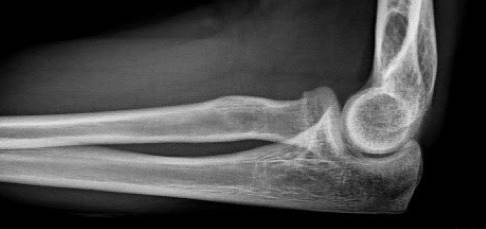

Apparative bildgebende Diagnostik: Röntgen

Die Standarduntersuchung ist die Röntgenaufnahme des Ellenbogens in zwei Ebenen. Dabei wird eine a.-p. Aufnahme angefertigt (anterior-posterior, d. h. der Strahlengang verläuft von von vorne nach hinten durch das Ellenbogengelenk). Zudem erfolgt eine seitliche Aufnahme des Ellenbogengelenks. Einfache Frakturen (Fraktur-Typ 1 und 2 nach Mason) können mit der Röntgenaufnahme sicher diagnostiziert werden.